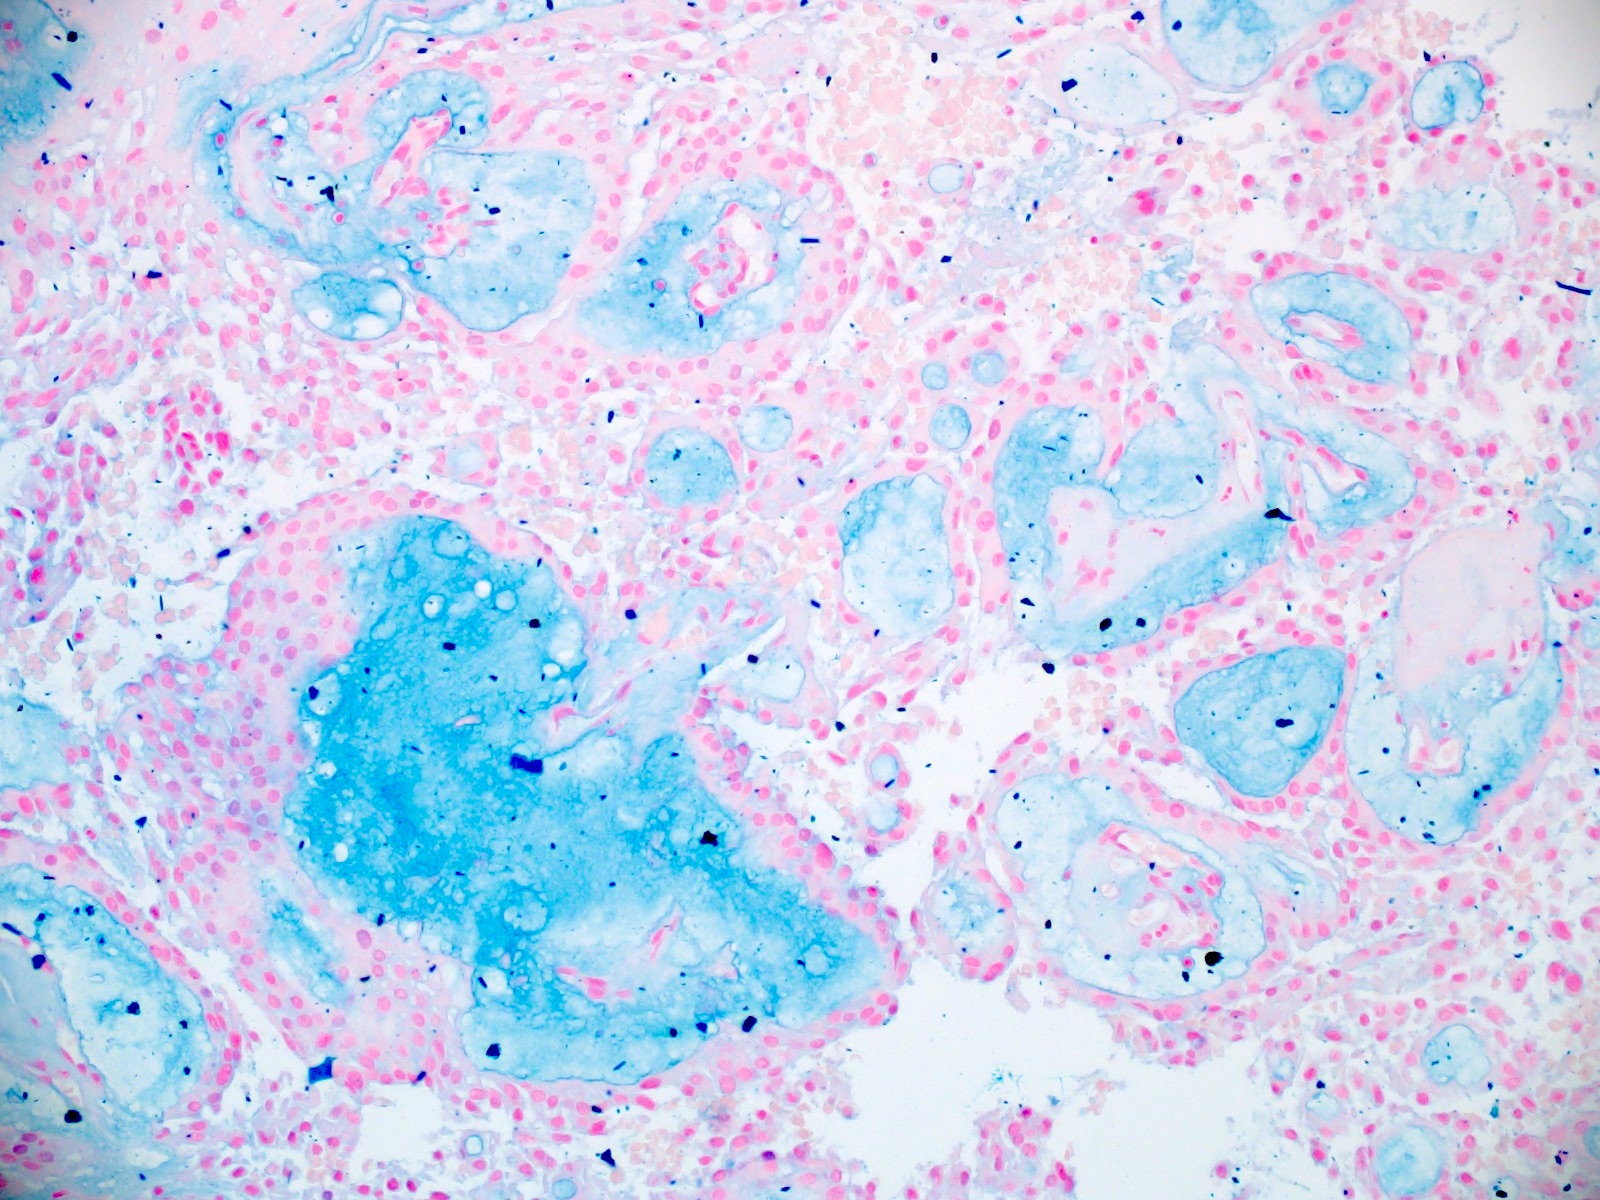

- Accumulation of basophilic myxoid material around blood vessels (myxoid stroma) and in microcysts

- Myxoid material is highlighted by PAS and Alcian blue positive staining

- In cases composed of confluent sheets of epithelioid cells with little or no papillary structures, PAS and Alcian blue positivity is useful in reaching a correct diagnosis

Microscopic (histologic) images